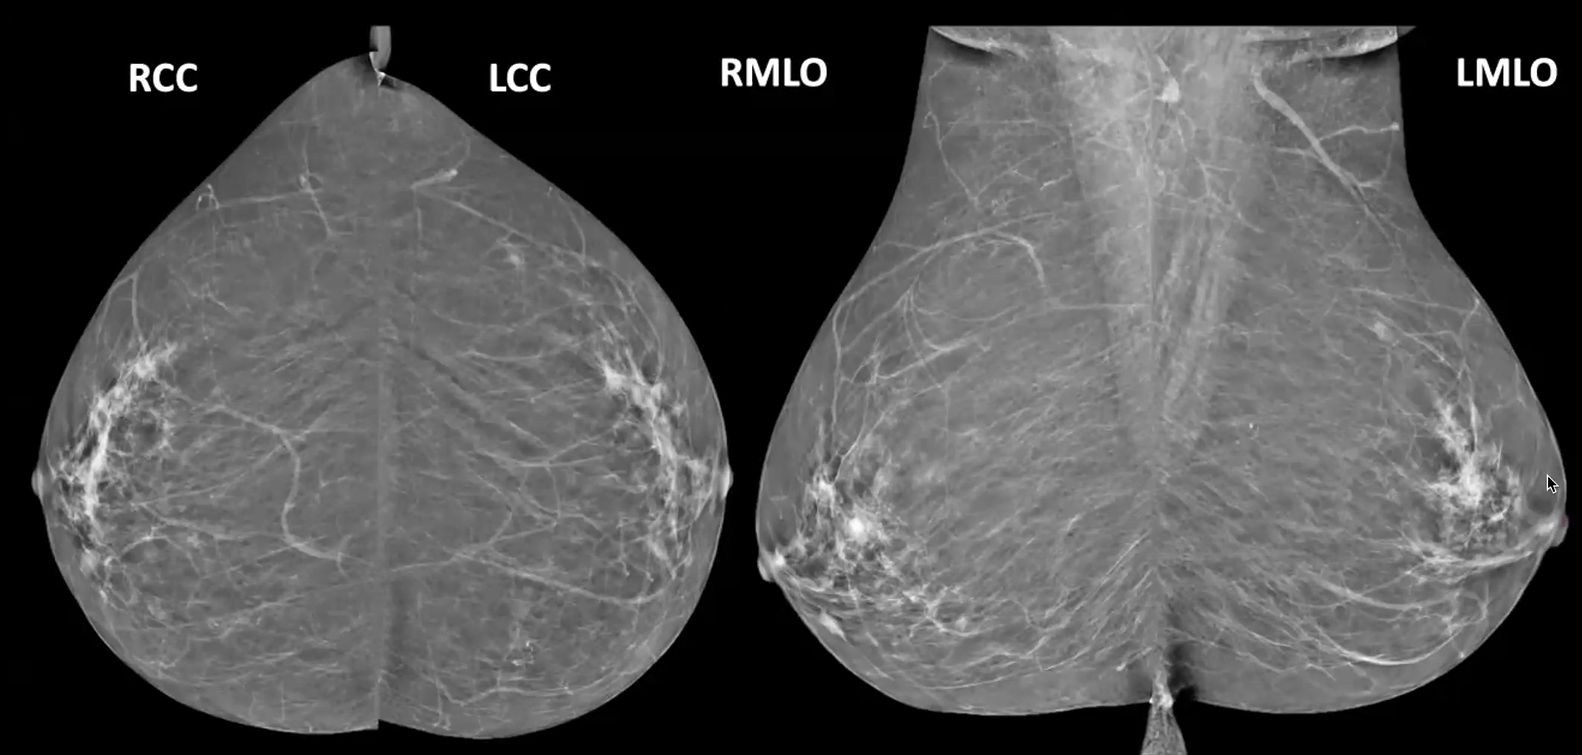

Mammogram views and Ultrasound scanning planes (Swipe left or right) Mammogram Views Learn Mammogram Markers Learn Ultrasound Scan planes Learn How to scan and survey the breast Learn